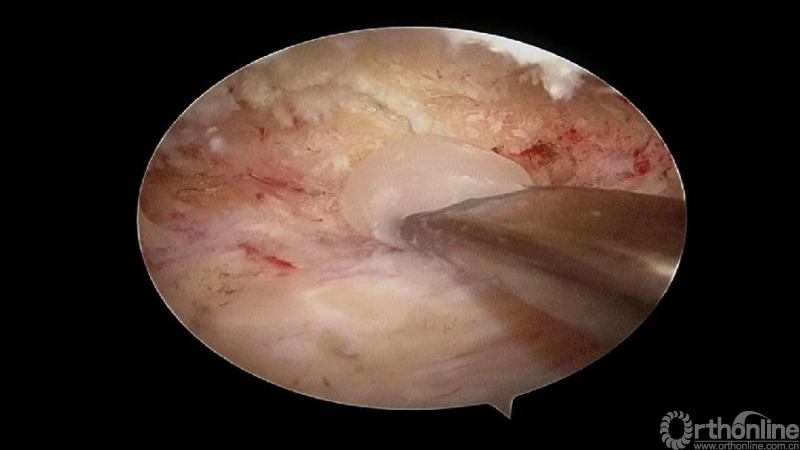

3.从游离骨块的背侧开始,用磨钻将骨块打薄,然后将骨块的底面与脊髓表面仔细分离,将游离骨块摘除;

4.进一步加深移除骨赘的残余部分,直到显露出对侧的神经根及关节突关节的内壁;